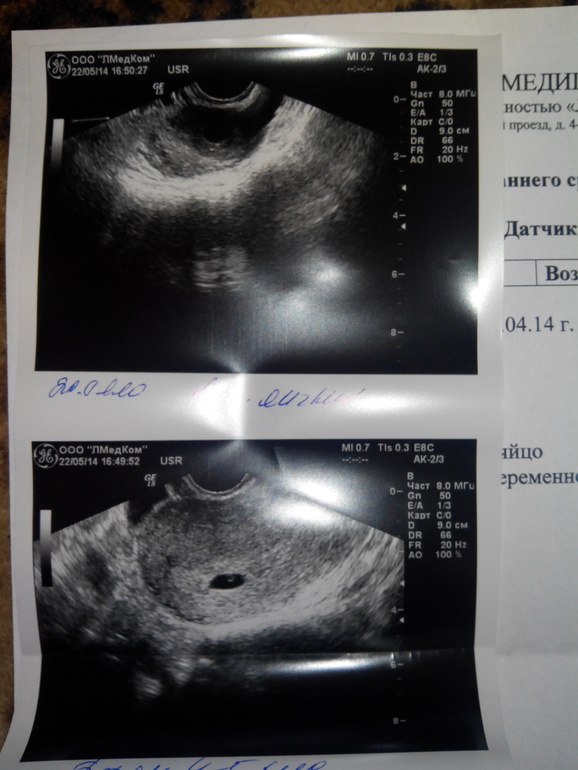

8 месяцев после чистки, 2 цикла после ОК,цикл регулярнейших ПА через "не могу")))

8 мая( 5 дн до М)ледичек

9мая эвик...ну и дальше уже 2 нед задержки))